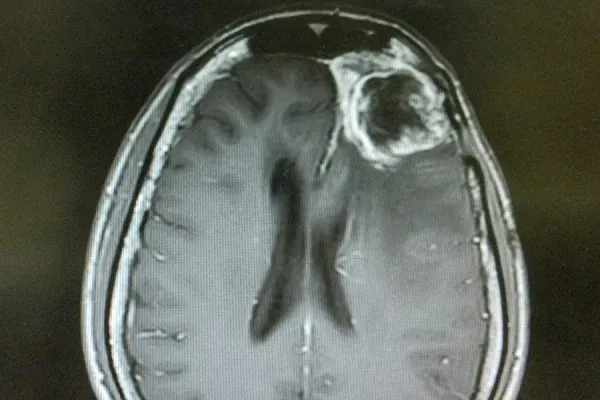

Rare cancers are those that affect fewer than 40,000 people per year in the U.S.* For multiple reasons, there is a gap in research support for rare cancers, which can limit research progress. Learn more about NFCR’s genomic approach which aims to benefit ALL types of cancers.